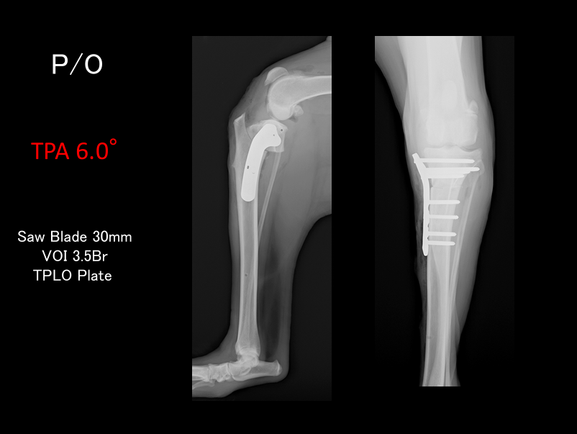

犬では膝関節の脛骨の関節面の角度が平均25°程度傾いています。脛骨近位を骨切りしてこの角度を0~6.5°程度に補正すると、前十字靱帯が断裂したままでも膝の不安定性が解消されるということがわかっています。

脛骨近位の関節の平らな場所(脛骨高平部)を水平にする手術なので、脛骨高平部水平化骨切り術(Tibial Plateau Leveling Osteotomy :TPLO)と呼ばれ、術後の成績が大変良いため、世界各国で行われるようになっています。

脛骨高平部角(TPA)が35°以上あるものは、傾斜角度がきつく、E-TPAといわれています。まるちゃんはTPAが36°でしたので、目標とする角度に矯正するには、骨片をかなり回転させることになります。E-TPAは骨同士の接触面積も少なくなるため,正確な整復とインプラントの設置が求められます。